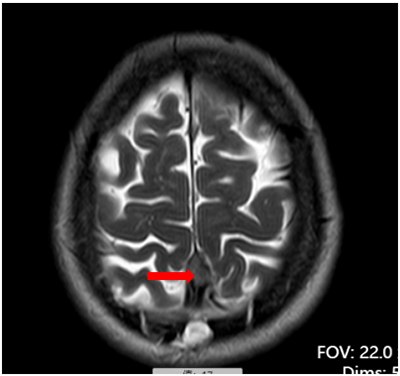

术前检查

术后复查,肿瘤消失